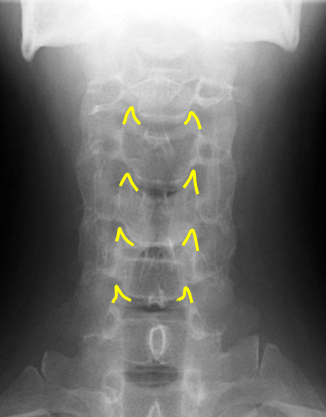

yellow

Occipital condyles

blue

Foramen magnum

C1 TVP/ lateral mass junction

Odontoid process

C2 spinous process

C2 pedicle shadow

Junction of lamina (top of spinous)

Uncinate processes